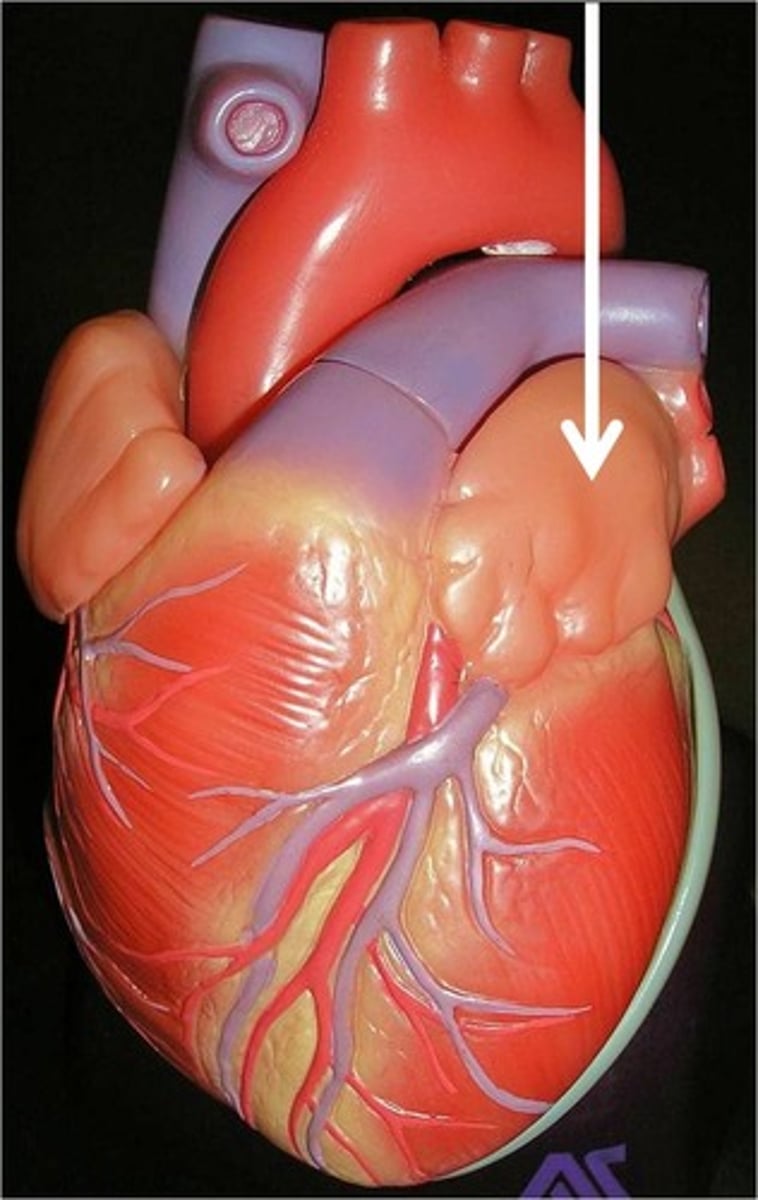

Pulmonary trunk

Collective structure. Leaves the right ventricle.